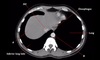

Name structures A to D

A - Aorta (ascending)

B - Aorta (descending)

C - Oesophagus

D - Trachea (at carina)